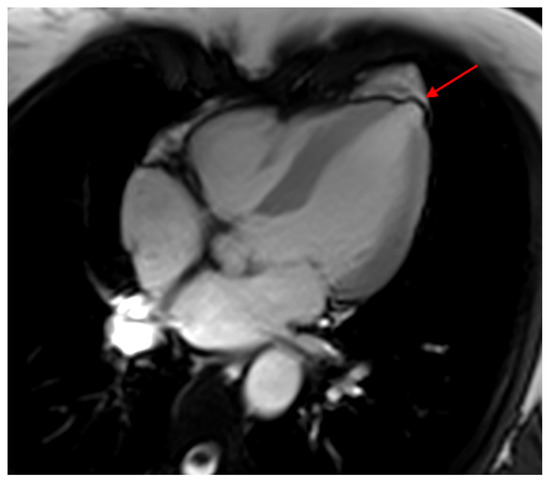

- Moll-Bernardes, R.J.; Saraiva, R.M.; Sarmento de Oliveira, R.; Tavares Pinheiro, M.V.; Camargo, G.C.; Xavier de Brito, A.S.; Altino de Almeida, S.; Siqueira, F.P.; de Souza Nogueira Sardinha Mendes, F.; Barbosa, R.M. Case Report: Malignant Ventricular Arrhythmias Mimicking Acute Coronary Syndrome in Chagas Disease. Am. J. Trop. Med. Hyg. 2020, 102, 797–799. [Google Scholar] [CrossRef]

- Senra, T.; Ianni, B.M.; Costa, A.C.; Mady, C.; Martinelli-Filho, M.; Kalil-Filho, R.; Rochitte, C.E. Long-term prognostic value of myocardial fibrosis in patients with chagas cardiomyopathy. J. Am. Coll. Cardiol. 2018, 72, 2577–2587. [Google Scholar] [CrossRef]

- Mello, R.P.D.; Szarf, G.; Schvartzman, P.R.; Nakano, E.M.; Espinosa, M.M.; Szejnfeld, D.; Fernandes, V.; Lima, J.A.; Cirenza, C.; De Paola, A.A. Delayed enhancement cardiac magnetic resonance imaging can identify the risk for ventricular tachycardia in chronic Chagas’ heart disease. Arq. Bras. Cardiol. 2012, 98, 421–430. [Google Scholar] [CrossRef]

- Volpe, G.J.; Moreira, H.T.; Trad, H.S.; Wu, K.C.; Braggion-Santos, M.F.; Santos, M.K.; Maciel, B.C.; Pazin-Filho, A.; Marin-Neto, J.A.; Lima, J.A. Left ventricular scar and prognosis in chronic chagas cardiomyopathy. J. Am. Coll. Cardiol. 2018, 72, 2567–2576. [Google Scholar] [CrossRef]